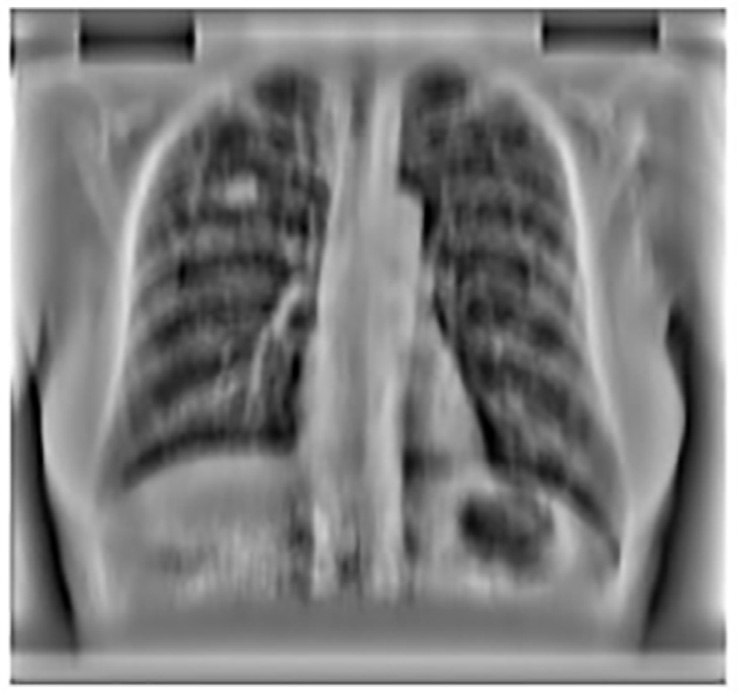

使用主成分分析滤波器进行肋骨抑制的结果如图14.2B所示。采用标准的高斯检测器高斯拉普拉斯掩模(LOG)来寻找可能存在结节的峰值区域。在原始胸部X光图像中应用该掩模导致了大量的假阳性,如图14.2A 所示,其中许多假阳性出现在肋骨上。

然而,在使用主成分分析滤波操作进行肋骨抑制后,该掩模除了检测到真正的结节外,仅产生了极少量的假阳性。人们认为,假阳性数量的减少主要归功于对肋骨的有效抑制。

应用PCA滤波后获得的图像如图14.8 所示,该图显示与使用均值滤波器提取的结果(如图14.5所示)相比,软组织受损更少。